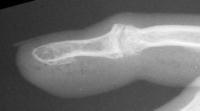

Distal interphalangeal erosive osteoarthritis severe enough that the diagnosis of giant cell or other tumor was suspected. Fortunately, no tumor was encountered at surgery.

The trial implant sizer shows the true size of the implant. The final implant has a radiolucent coating  which makes it appear smaller than it is on Xray.

Final implant radiographs.